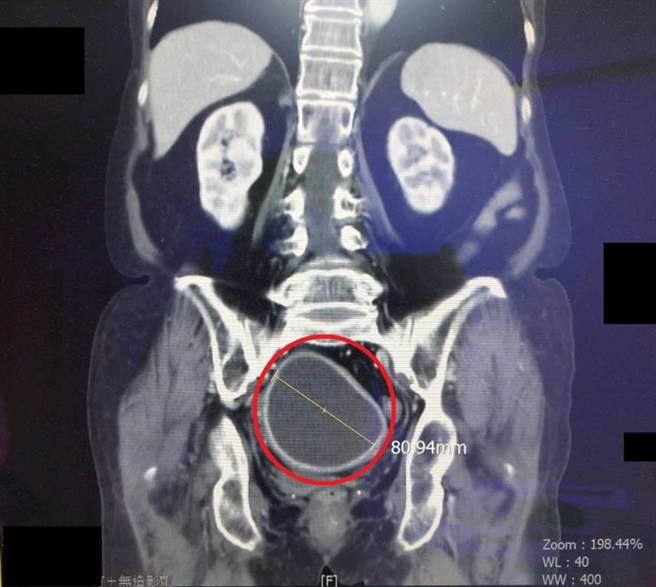

李姓老妇因下腹痛长达3个月到医院就医,经医师电脑断层检查发现,疑似有高达8公分的腹部肿瘤,并推测出可能是子宫病变或囊肿,需要接受手术治疗,但她3年前曾发生自发性直肠穿孔及化脓,歷经手术与半年时间的人工肛门治疗,其腹部沾黏非常严重,若再次手术恐造成许多问题。

经过妇产科、外科和放射科医师共同讨论后,决定先以子宫镜搭配超音波导引治疗,同时也预备子宫切除大手术。医师透过子宫镜检查发现,疑似肿瘤的地方竟有一大片的子宫化脓,当下随即处理,成功在15分钟内引流脓疡,而且病理切片为良性,在经过抗生素治疗1周后,就顺利康復出院,让李姓老妇不必再经歷一次大手术。